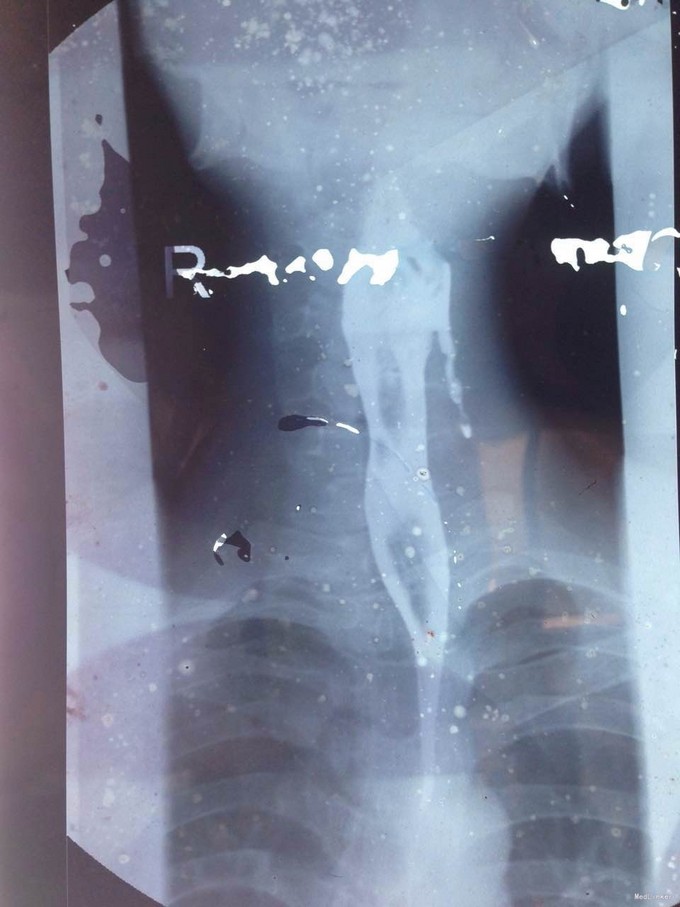

该患者在诊断上是有些困难,颈部多发脓肿是明确的,但是瘘口的位置不好确定,从而未能确诊,8年前患者行上消化道钡餐检查,诊断“食管瘘”,但是我们从8年前的影像上看,瘘口的位置太高,不像是食管的瘘口,考虑是不是梨状窝的瘘道,为了进一步确诊,我们给患者行了胃镜检查,结果胃镜发现左侧梨状窝有1个3mm大小的小孔,胃镜未能通过,食管未见明显的瘘口。为了更加明确瘘口的位置,我们与影像科商议后决定口服造影剂后行颈部CT平扫,因怕钡餐沉积在脓肿内不好排出,我们采用了口服碘化油。此次影像明确了瘘口的确在左侧梨状窝。最终诊断:左侧颈部多发脓肿;左侧梨状窝瘘道形成。 治疗:入院后予抗感染、禁食、营养支持等治疗,患者感染得以控制,请耳鼻咽喉科会诊后建议转科治疗。